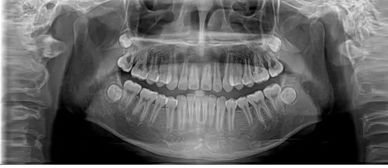

任何一家稍微上規(guī)模一些的口腔門診或者醫(yī)院都會(huì)帶有微焦牙片機(jī)的.

拍攝牙片時(shí)只需要大張口,待醫(yī)生擺好拍攝角度后,不要亂動(dòng)并用手按好牙片即可.幾秒鐘后牙片就能拍攝好,沖洗出來(lái)也不過(guò)2分鐘而已.

因?yàn)檠榔瑱C(jī)是微焦的,所以輻射要相對(duì)于其他骨科片要小的多,偶爾拍攝一張沒(méi)有什么影響的,所以不用擔(dān)心.

在哪拍牙片都是一樣的,主要看的就是醫(yī)生的技術(shù),只要清晰能看到病變區(qū)就OK了.費(fèi)用很低,我們這邊是10元,不過(guò)這要以你們當(dāng)?shù)氐膬r(jià)錢為準(zhǔn).